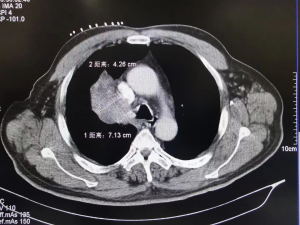

Precise Insertion of the Ablation Needle under CT Guidance

On the day of the surgery, under real-time CT guidance, the ablation needle was accurately inserted into the tumor tissue to perform the alternating cold and hot ablation treatment. The surgery was successfully completed.